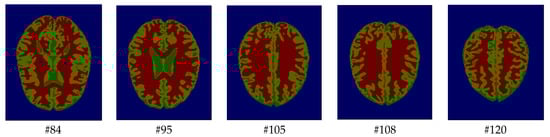

As mentioned before, the images of the first five datasets in Table 3 were used to evaluate the performance of the HMRF-WOA. Figure 1, Figure 2, Figure 3, Figure 4 and Figure 5 show some slices of a T1-weighted image (slices: 84, 95, 105, 108, 120). These brain images correspond to the slices under different types of conditions, such as database type, dimension image, noise level, intensity non-uniformity level, and slice thickness (mm). In Table 1, rows 1 to 5 summarize the parameters of Figure 1, Figure 2, Figure 3, Figure 4 and Figure 5, respectively. Figure 6 represents the ground truth segmentation of slices 84, 95, 105, 108, and 120. In this figure, each column contains the three tissues, GM, WM, and CSF, of each slice. Figure 7, Figure 8, Figure 9, Figure 10 and Figure 11 show the segmentation results, where the four tissues (BG, GM, WM, and CSF) are shown with different colors. The yellow, red, and green colors represent the segmented regions of GM, WM, and CSF, respectively. As we can also see from these figures, the resulting segmented images in Figure 7, Figure 8, Figure 9, Figure 10 and Figure 11 are almost close to the initial images in Figure 1, Figure 2, Figure 3, Figure 4 and Figure 5.

The qualitative analysis provides a visual representation of the segmentation approaches. The visual comparison of the resulting images using the HMRF-WOA appears to be more similar to the reference image (ground truth), where Figure 1, Figure 2, Figure 3, Figure 4 and Figure 5 show the GM, WM, and CSF tissue regions of the reference image with higher values of noise levels (3, 5, 7, and 9%) and intensity non-uniformity levels (20, 40%), whereas Figure 7, Figure 8, Figure 9, Figure 10 and Figure 11 show the subject images obtained using the proposed technique. However, this result shows that with higher values of noise and intensity non-uniformity, the algorithm, with its hyperparameters, is able to segment the tissue regions correctly.

Figure 1. Slices with Noise = 0%, INU = 0% of database 1.